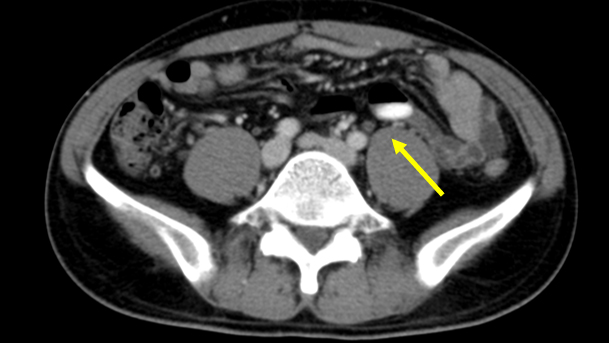

No. 154 症例4:30歳代男性

• 右頸部に多発する嚢胞性(または壊死性)病変、リンパ節腫大

• 脾多発腫瘤、脾門部多発リンパ節腫大

• 腸管内に錠剤あり